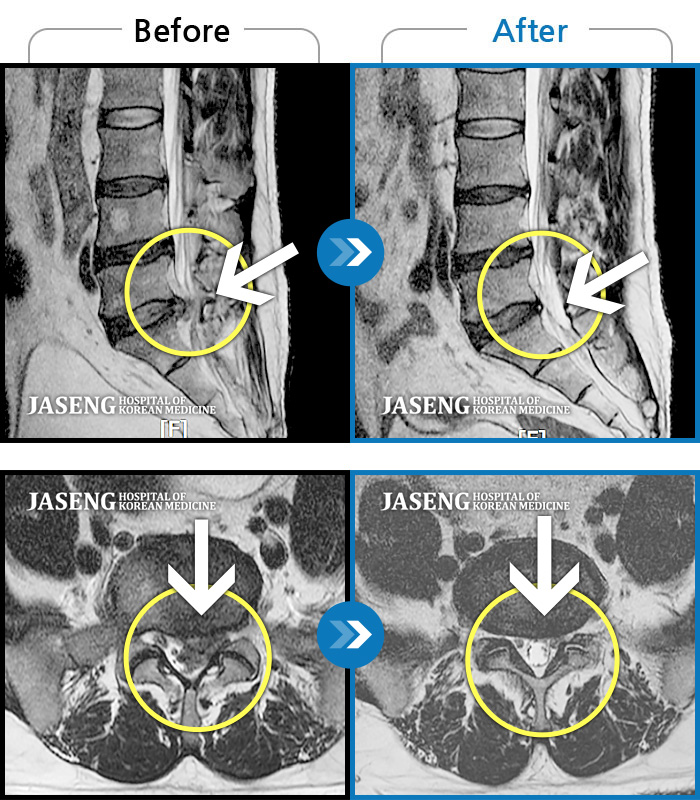

허리디스크

많이 본 사례

인천 · 조남훈 원장

계속 아파서 일을 일주일에 2번밖에 못해요.

촬영시기

2019.11.23 ~ 2023.12.15

2023.12.20

조회수 445